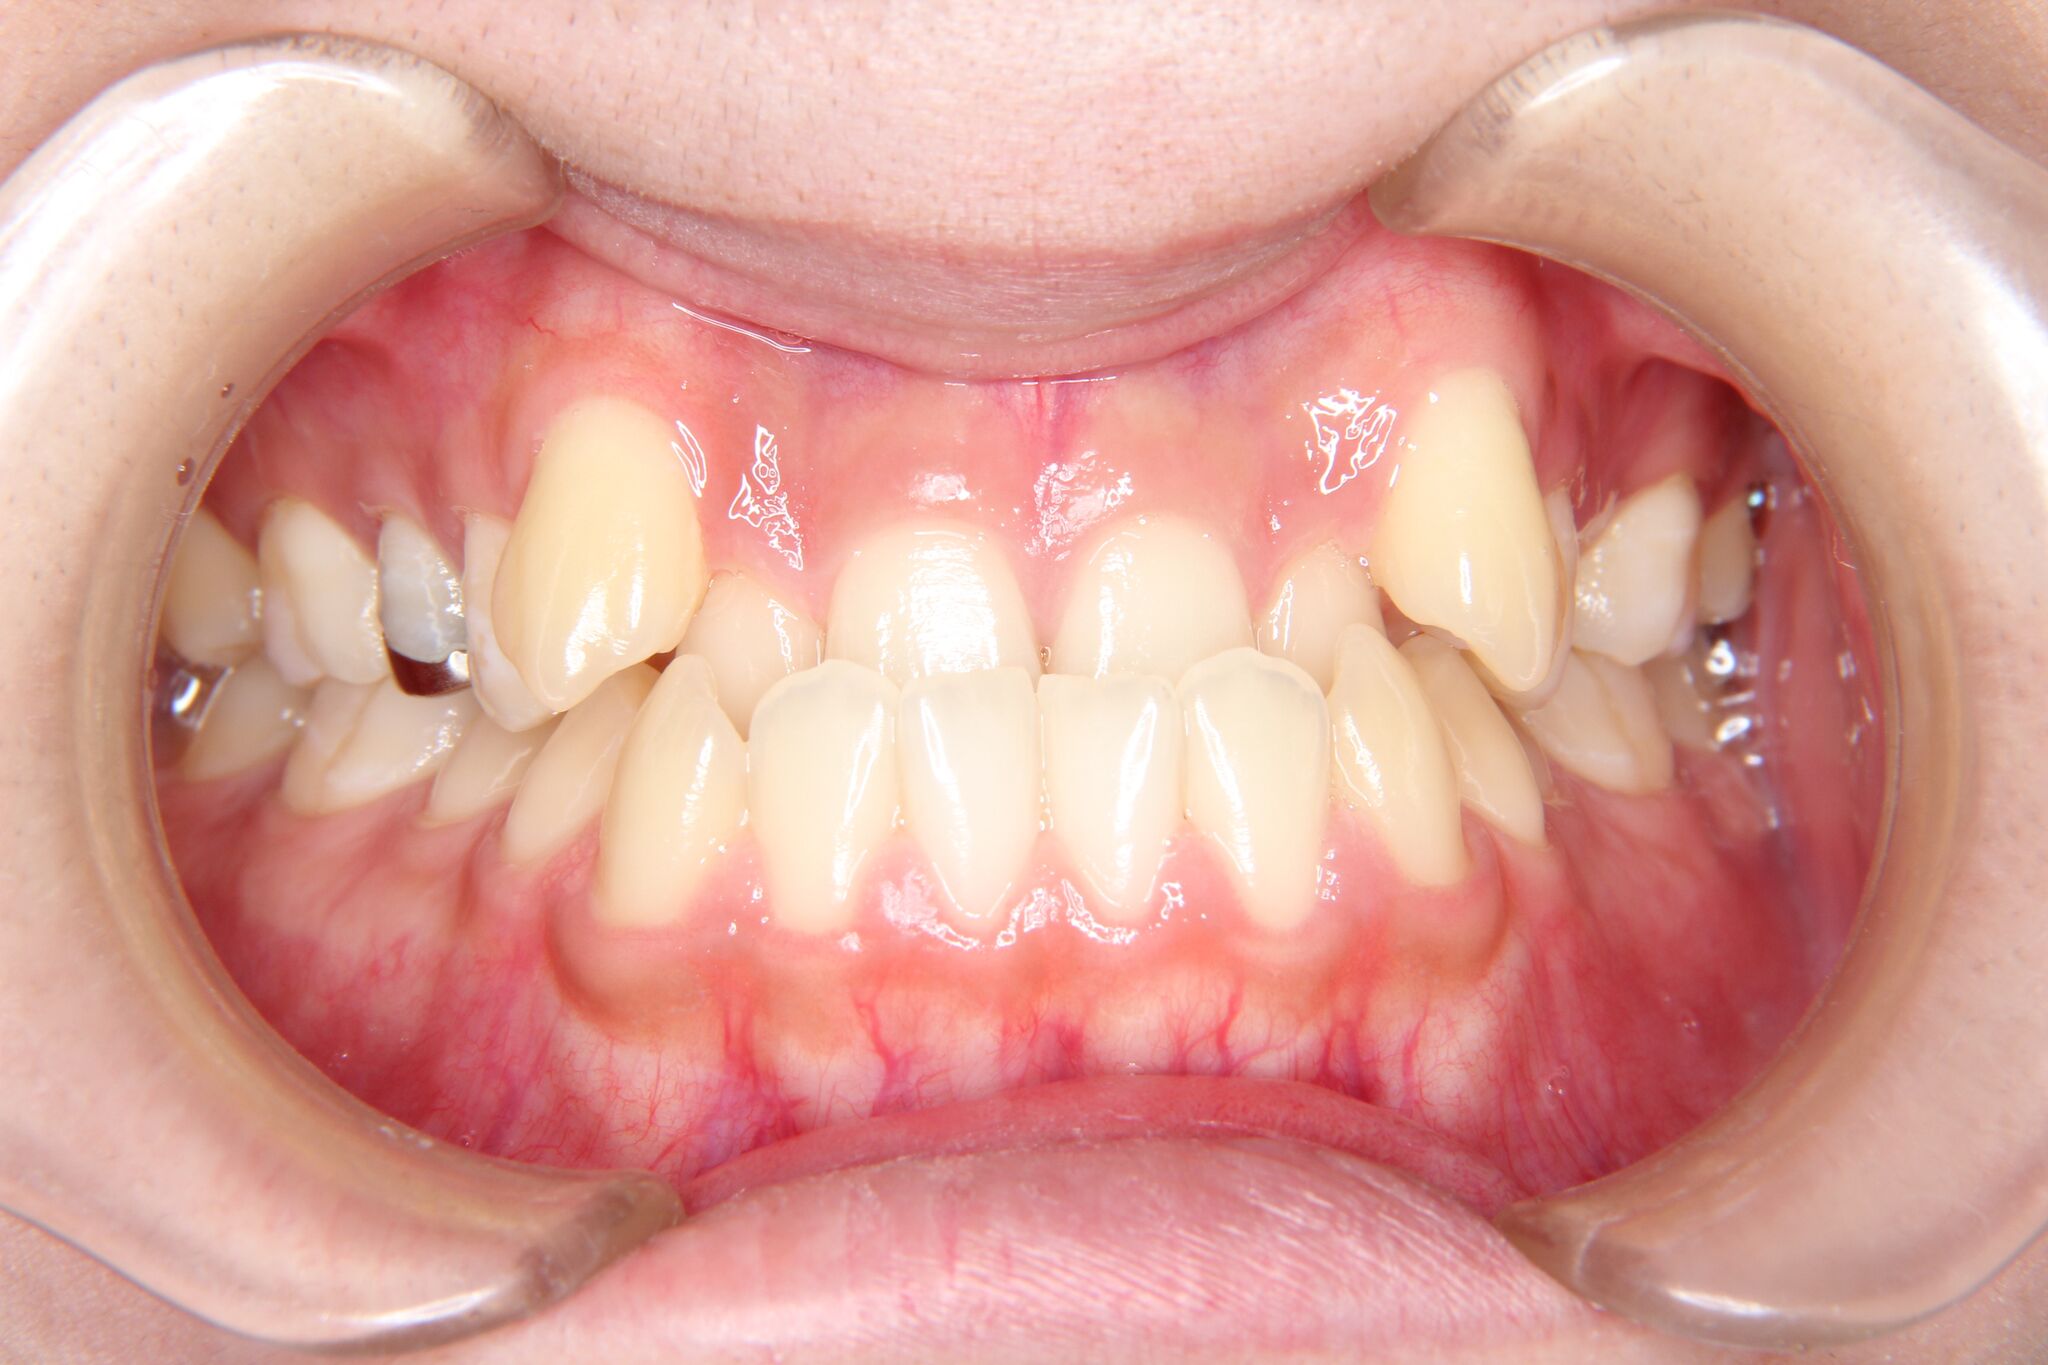

受け口

反対咬合(上顎前歯部叢生)

【患者】 10代 男性

【期間】 1年5カ月

- 治療前 治療後

非抜歯で治療を行いました。

- 上顎大臼歯部の遠心移動

- 下顎歯列全体のアップライティング